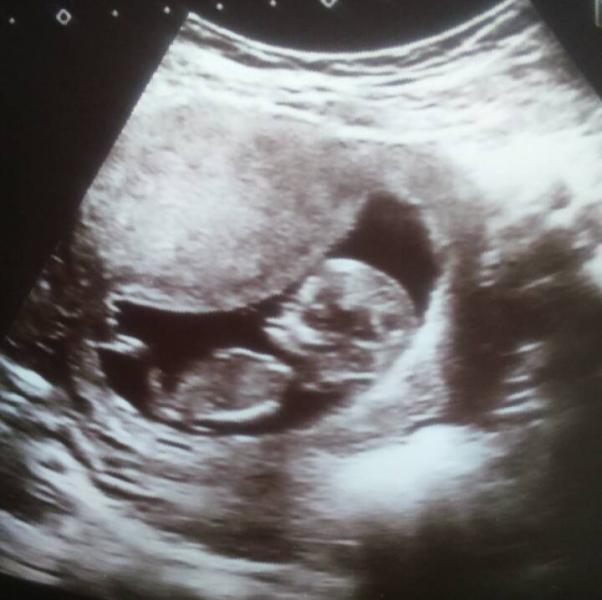

сделали УЗИ))

все хорошо, срок 12 недель,

сердцебиение 152 удара

рост 51мм

по задней стенке прикреплен 😍

предположений относительно пола не делали, так как рано еще,

лялька крутилась, вертелась ничего бы и не увидели.